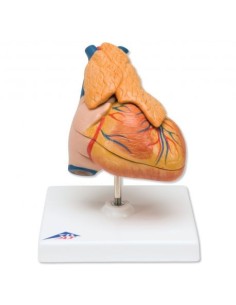

Du crâne en 22 parties à verrouillage magnétique aux modèles de colonne vertébrale, des modèles d'articulation aux modèles de cœur, chaque pièce de notre collection est conçue pour une immersion totale dans l'étude de l'anatomie humaine. Nos modèles, réalisés à partir de scans d'os réels, garantissent une expérience tactile authentique et une fidélité de poids presque identique aux originaux.